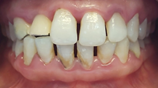

(Figures 13–20) All ceramic crown with a zirconia framework would provide an acceptable aesthetic result. Zirconia framework always requires a try-in step to confirm fit, insertion, retention, and mostly the space left for cosmetic ceramic. After veneering with feldspathic ceramic, and intraoral checking, crowns were glazed, then cemented: A good aesthetic integration was observed: respect of the shape, volume and color of the tooth compared to its counterpart with well distributed diastemas.

Figure 19 Final result: discreet smile.

An asymmetry of the neckline persisted after the prosthesis was placed, but this did not bother the patient, since her smile is purely dental. Functionally, care was taken to integrate the prosthesis into the patient's occlusal context while paying attention to the aesthetic aspect (situation of the free edge of the prosthesis).